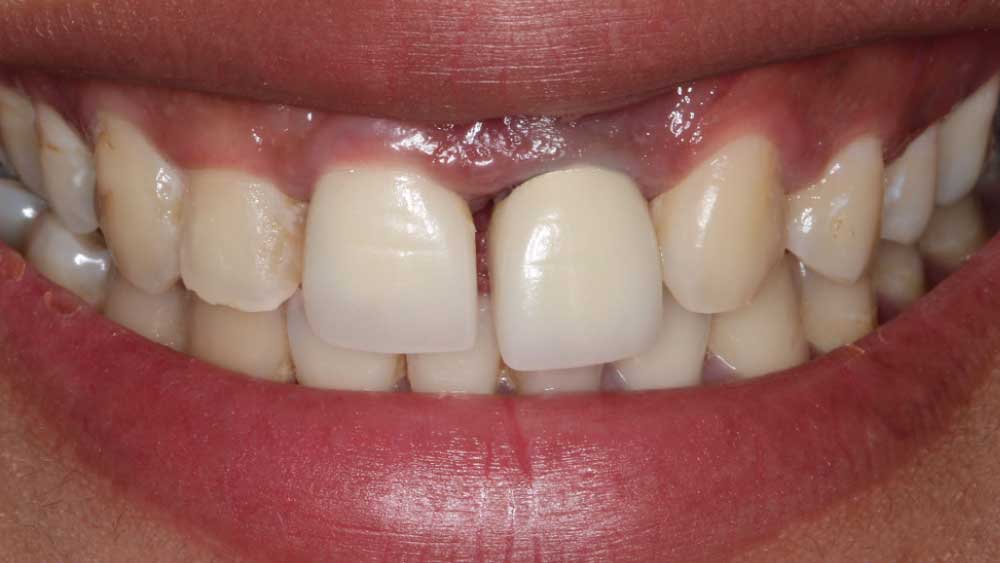

After conducting a thorough diagnostic examination, a vertical root fracture was noted, leaving the #9 central incisor malaligned and unstable. Due to the presence of significant vertical bone loss, extensive treatment for guided bone regeneration and a connective tissue graft would have been required prior to implant placement. After the patient was consulted on these factors, she opted against implant treatment. Once we discussed the remaining options, she decided on a bridge from #8–11 and a veneer on #7. Because she was congenitally missing tooth #10, placing a bridge to restore the edentulous area required preparing the adjacent canine and reshaping it to look like the missing lateral. I selected BruxZir® Esthetic Solid Zirconia as the best material to restore her beautiful smile. Not only does BruxZir Esthetic have superior strength compared to similar all-ceramic materials such as IPS e.max®, but it also has a translucent, natural-looking appearance. Sometimes clinicians think it is risky to do an all-ceramic bridge, but with a strong material like BruxZir Esthetic that has an average flexural strength of 870 MPa, doctors can confidently seat an anterior bridge that will produce long-lasting results. BruxZir has become such a popular material for dentists that it has been utilized to successfully fabricate more than 1.2 million bridges.

It was a four-month restoration process but a worthwhile journey. The outcome radically transformed Maria’s life. She no longer struggles to eat certain foods, nor does she lack confidence in her appearance. Instead, she feels great about herself and is able to talk confidently in front of people. Her BruxZir Esthetic veneer and bridge have given her a new lease on life. Now she is no longer afraid to share her smile with the world.